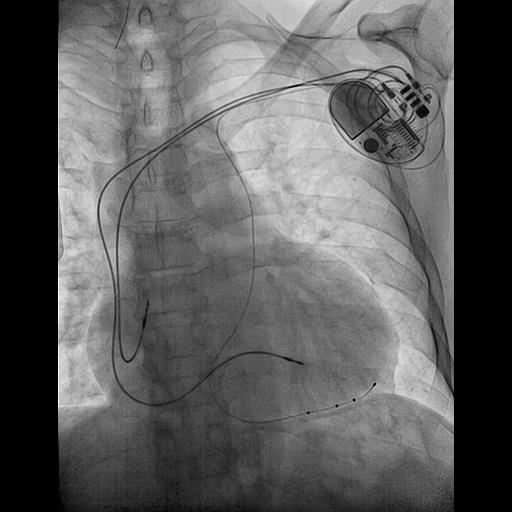

@ShaojieChen1 @hrs_journal @dredcronin @TJaredBunch @d_changy @DanielPMorin @drrakeshg1 @Maeskander @senthil_dorai @DrRoderickTung @pjsm83 @mencardio @ZS279 @clementy_ep @MBergonti @Anand_Ganesan1 @RawahiAl @javadm20 @rdschaller @SchakrabartiEP @EJSMD @LaredoMikael @ugurcanpolatmd @ChiaraValeriano @MDerndorfer @ecgrhythms @adribaran @Basalus @jvillacastin @DrGregMichaud nsHBP, sHBP, LVSP, sLBBP, nsLBBP, LBBAP, LVSP, RVSP, nsRBBP, sRBBP, what should we look forward to next?